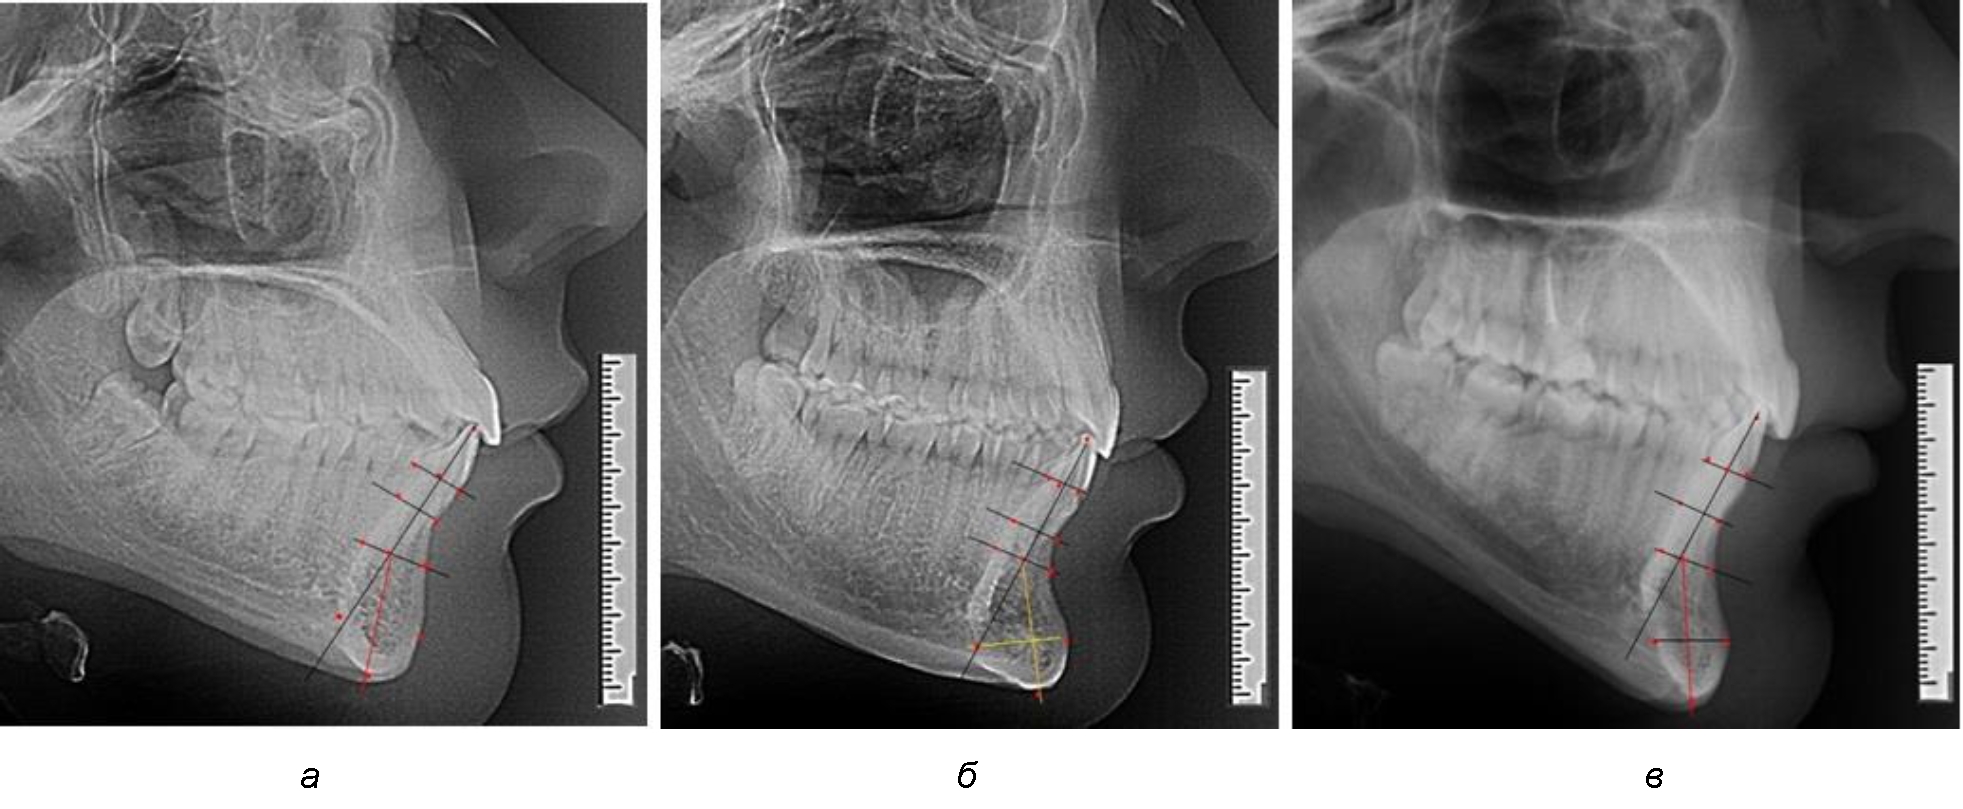

На нижнем контуре подбородочного выступа определяли положение ментальной точки Me. Линия, соединяющая апикальную точку с ментальной, определяла высоту подбородочного выступа тела нижней челюсти. Высота зубочелюстного сегмента IsL–Ме измерялась от резцовой до подбородочной точки. Вертикальная линия Ap–Me делила подбородочный выступ на две части: переднюю и заднюю (рис. 1).

Рис. 1. Ориентиры для исследования нативных препаратов (а) и рентгенограмм (б) резцового нижнечелюстного сегмента

Сагиттальные размеры зубоальвеолярной части сегмента определялись между точками Bsm и Bsm', в апикальной части сегмента – B и B'. В подбородочной части сегмента из передней выступающей точки подбородка Pog проводили линию перпендикулярно к линии Ар–Ме с определением точки Pog'. Расстояние Pog–Pog' определяло ширину подбородочного выступа.

При анализе полученных данных обращает на себя внимание факт того, что из вертикальных параметров зубоальвеолярной части сегмента наиболее вариабельным является размер между апикальными точками Downs и Schwarz (BSM–B), который составлял (6,79 ± 0,54) мм, при величине сигмального отклонения – 2,35. Также большая ошибка репрезентативности и сигмальное отклонение было отмечено при оценки ширины подбородочного выступа. В связи с этим встречались варианты резцовых сегментов нижней челюсти различные как по ширине, так и по высоте, а также по расхождению положения апикальных точек по Downs и Schwarz (рис. 3).

Рис. 3. Варианты среднего (а), широкого (б) и узкого (в) нижнечелюстного резцового сегмента

Варианты резцовых сегментов нижней челюсти различные как по ширине, так и по высоте, а также по расхождению положения апикальных точек по Downs и Schwarz представлены на рис. 4.

Рис. 4. Особенности нижнечелюстного резцового сегмента на ТРГ у людей при среднем (а), широком (б) и узком (в) вариантах